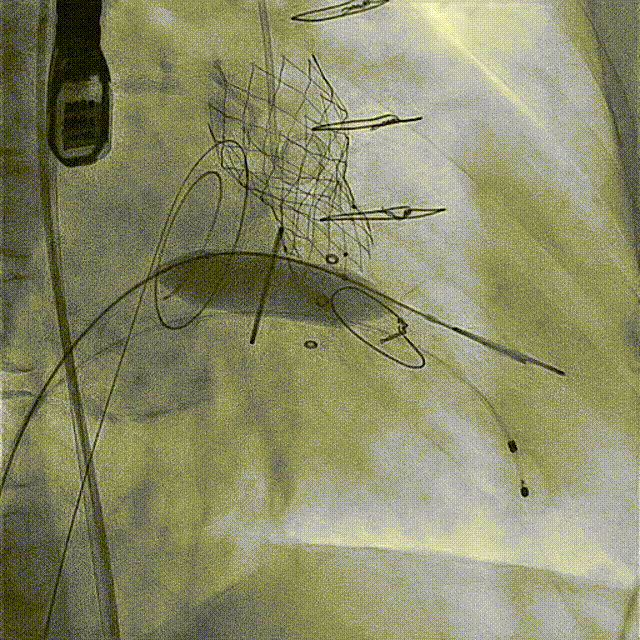

患者手术过程顺利,穿刺右侧股动脉作为TAVR路径,右侧股静脉作为TMVR路径。通过食道超声指引房间隔穿刺,在卵圆窝偏下后方位置顺利进入左房,留置钢丝后全身肝素化;通过右侧股动脉植入20F GORE鞘,按照常规TAVR流程,在主动脉瓣成功进行人工主动脉植入,测定术后压差为0 mmHg。然后通过左房留置钢丝交换可调弯鞘,帮助顺利跨瓣,再次将鞘交换为14 F E-sheath后,在二尖瓣生物瓣位置顺利完成瓣中瓣植入,术后即刻二尖瓣平均跨瓣压差降至4 mmHg。双瓣置换手术成功完成。